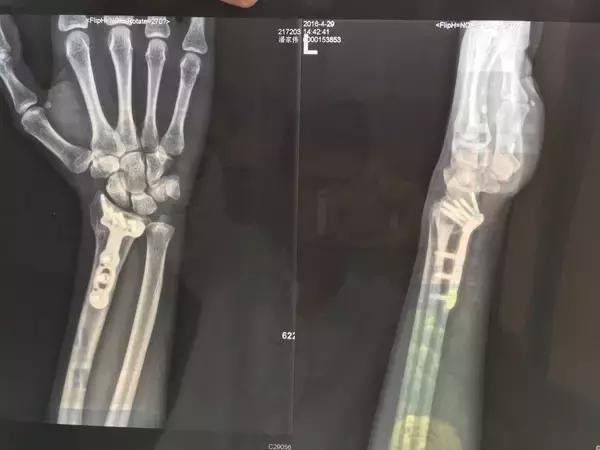

HardFlip砍到迎面骨什么的就不说了,直接贴一张下碗的图吧

在中山公园耍贱从5格台阶位置想跳下来,自以为摔跤了不过滚两圈的事儿,就没多想,结果可想而知。手腕好痛!!!坐起来一看,手腕断的角度说实话也是让我吃了一惊。打车到六院,拍片子一看,骨折了,要开刀,这个不太好开,联系你家人吧。我当时的内心的崩溃的我要死了我以后要成杨过了。可能现在开刀都是打局部麻醉的?我只能听见在手术室叮叮当当和锯子锯我骨头的声音,医生们还边手术边开我玩笑,天呐小伙子你怎么断成这样啊?我笑得出嘛我T T。开完刀叫一个疼,毕竟是骨头被打了几个孔用钢板固定在一起的。